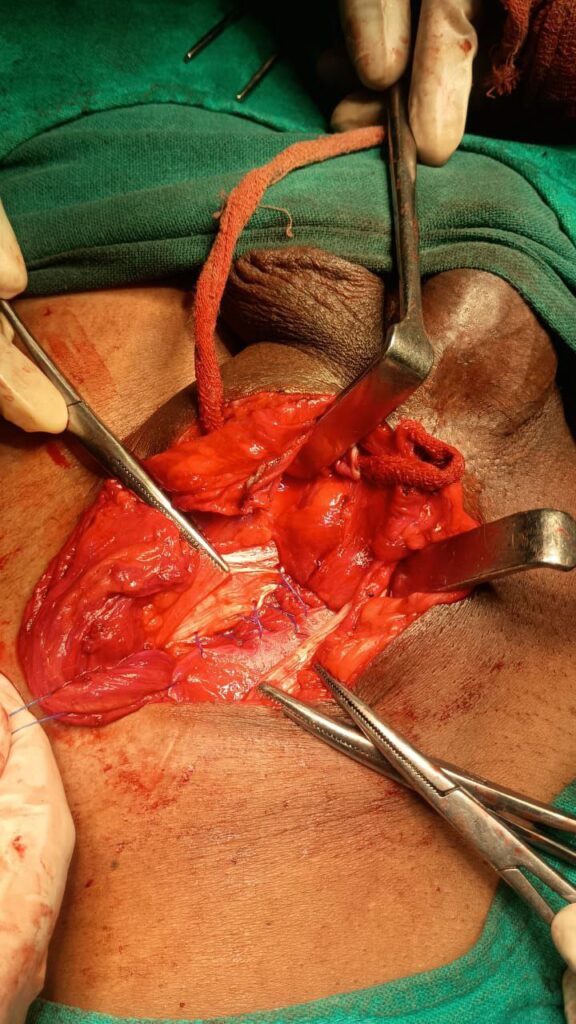

It was our surgery Unit-4 Admission day…

we done the duties , I was posted in EMOT, I got a chance to do some minor OTs then at around 7pm an obstructed inguinal hernia patient came then we prepared the patient for the emergency OT. and at the end of the day I got a chance to see the Darnes procedure in emergency hernia repair of the patient.